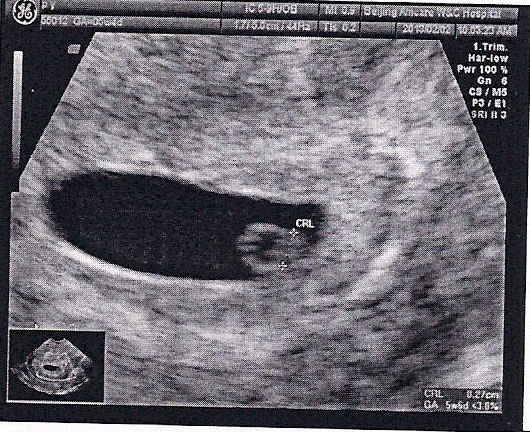

21 дпп узи

21 дпп узи 118 фото